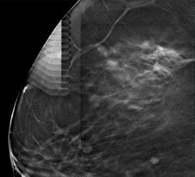

- 1유방촬영술(3D Tomosynthesis)로 미세석회화의 위치를 확인

- 2진공보조흡입장치를 미세석회화에 위치시킨 후, 조직을 획득

- 3검체 획득 후 석회화 병변 부위가 빈공간이 되어 까맣게 뚫린 것을 확인

- 4획득한 검체를 촬영하여 미세석회화를 확인